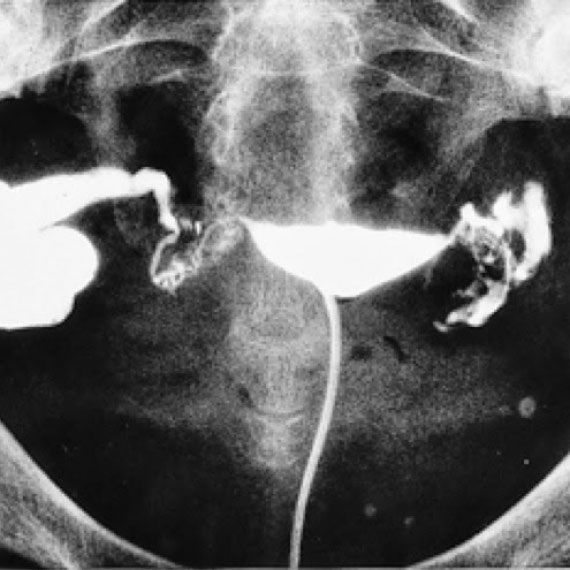

- تصوير الرحم والبوق (Hysterosalpingography) – خلال هذا الفحص، يتم إدخال مادة يمكن تمييزها بواسطة التصوير، إلى عنق الرحم. من خلال الصورة، من الممكن رؤية مبنى الرحم وقنوات فالوب وتشخيص العيوب البنيوية والتشريحية المختلفة التي تعيق حدوث الحمل.